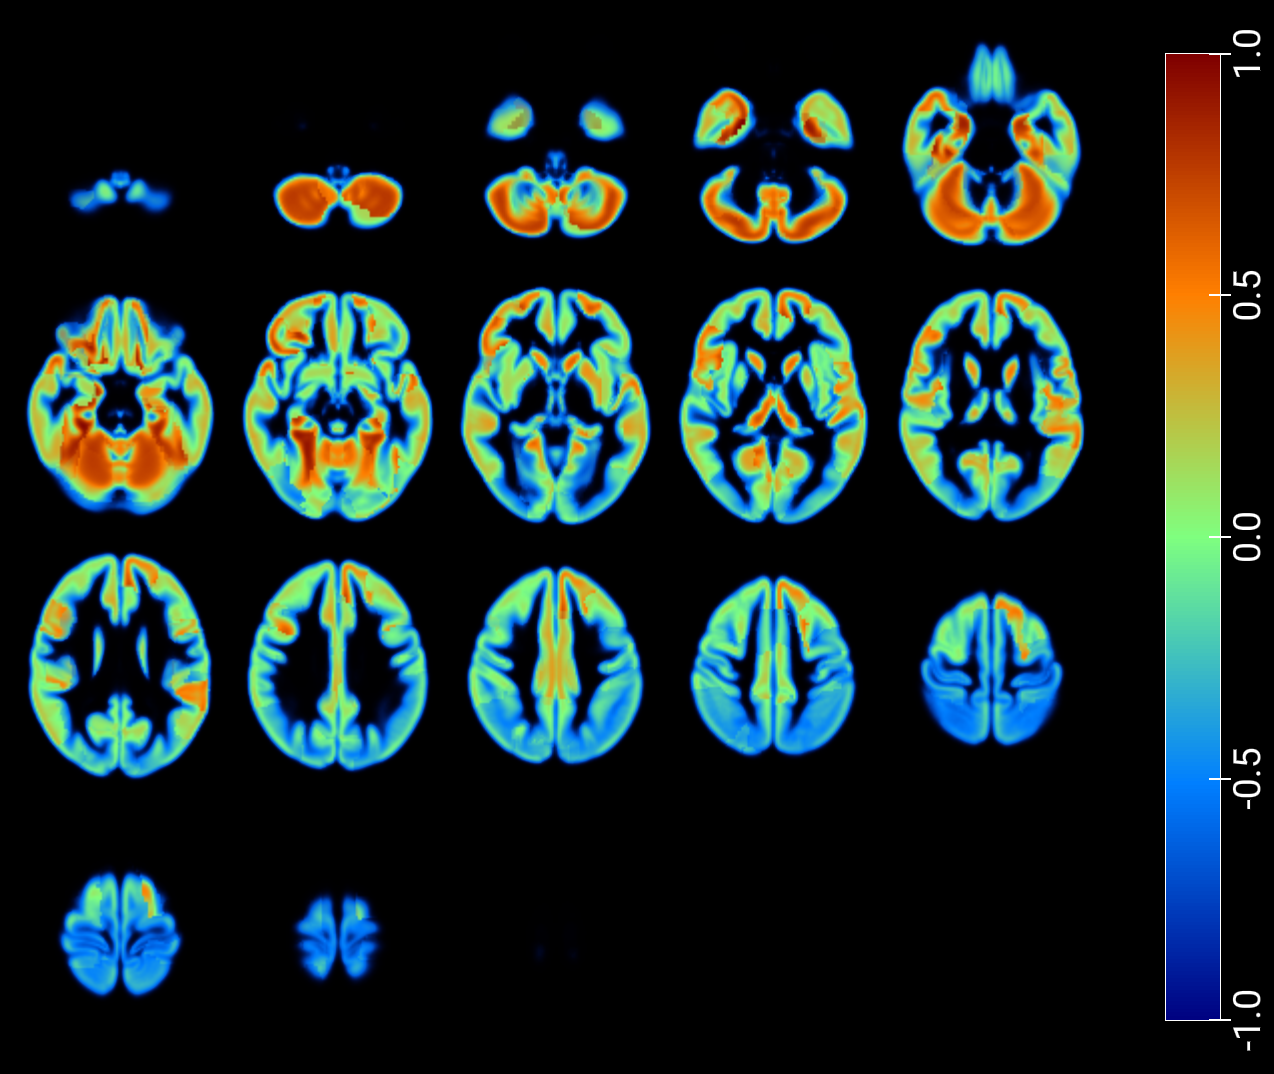

As a critical baseline, we report classification results based on latent features in [2] and provide visualizations of the maximum Pearson correlation values between latent-space activations -projected onto low-dimensional spaces- and region-wise average intensities, stratified by class, and fused with GM MRI (figures 7 and 8). These results explore the correspondence between network activations and anatomical signal distributions and whether it differs across clinical conditions (e.g., AD vs. NOR). This offers a transparent alternative to assess model interpretability and underscores the need for more rigorous and nuanced validation practices in the field.

An inspection of the groups and regions with the highest correlations reveals overlapping areas across clinically relevant comparisons in image reconstruction, as summarized for the t-SNE–based projections in Table 2. These regions correspond closely to those identified through the SHAP analysis presented in the following section (Table 3).

| NOR, AD | NOR, MCI | Cingulum_Mid_R, Frontal_Mid_L, Insula_R |

| NOR, MCI, MCIc, AD | Cerebelum_Crus2_R, Frontal_Mid_L, Insula_R | |

| NOR, MCIc | Frontal_Mid_L, Frontal_Mid_R, Frontal_Sup_L | |

| NOR, MCI | NOR, MCI, MCIc, AD | Frontal_Inf_Oper_L, Frontal_Mid_L, |

| Insula_R, Temporal_Mid_L | ||

| NOR, MCIc | Frontal_Mid_L, Temporal_Mid_L | |

| NOR, MCI, MCIc, AD | NOR, MCIc | Frontal_Mid_L, Heschl_L, Temporal_Mid_L |